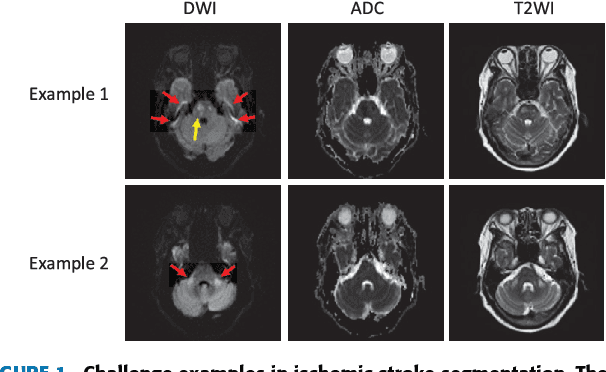

Abstract:Ischemic stroke is a common disease in the elderly population, which can cause long-term disability and even death. However, the time window for treatment of ischemic stroke in its acute stage is very short. To fast localize and quantitively evaluate the acute ischemic stroke (AIS) lesions, many deep-learning-based lesion segmentation methods have been proposed in the literature, where a deep convolutional neural network (CNN) was trained on hundreds of fully labeled subjects with accurate annotations of AIS lesions. Despite that high segmentation accuracy can be achieved, the accurate labels should be annotated by experienced clinicians, and it is therefore very time-consuming to obtain a large number of fully labeled subjects. In this paper, we propose a semi-supervised method to automatically segment AIS lesions in diffusion weighted images and apparent diffusion coefficient maps. By using a large number of weakly labeled subjects and a small number of fully labeled subjects, our proposed method is able to accurately detect and segment the AIS lesions. In particular, our proposed method consists of three parts: 1) a double-path classification net (DPC-Net) trained in a weakly-supervised way is used to detect the suspicious regions of AIS lesions; 2) a pixel-level K-Means clustering algorithm is used to identify the hyperintensive regions on the DWIs; and 3) a region-growing algorithm combines the outputs of the DPC-Net and the K-Means to obtain the final precise lesion segmentation. In our experiment, we use 460 weakly labeled subjects and 15 fully labeled subjects to train and fine-tune the proposed method. By evaluating on a clinical dataset with 150 fully labeled subjects, our proposed method achieves a mean dice coefficient of 0.639, and a lesion-wise F1 score of 0.799.

Abstract:The patient with ischemic stroke can benefit most from the earliest possible definitive diagnosis. While the high quality medical resources are quite scarce across the globe, an automated diagnostic tool is expected in analyzing the magnetic resonance (MR) images to provide reference in clinical diagnosis. In this paper, we propose a deep learning method to automatically segment ischemic stroke lesions from multi-modal MR images. By using atrous convolution and global convolution network, our proposed residual-structured fully convolutional network (Res-FCN) is able to capture features from large receptive fields. The network architecture is validated on a large dataset of 212 clinically acquired multi-modal MR images, which is shown to achieve a mean dice coefficient of 0.645 with a mean number of false negative lesions of 1.515. The false negatives can reach a value that close to a common medical image doctor, making it exceptive for a real clinical application.